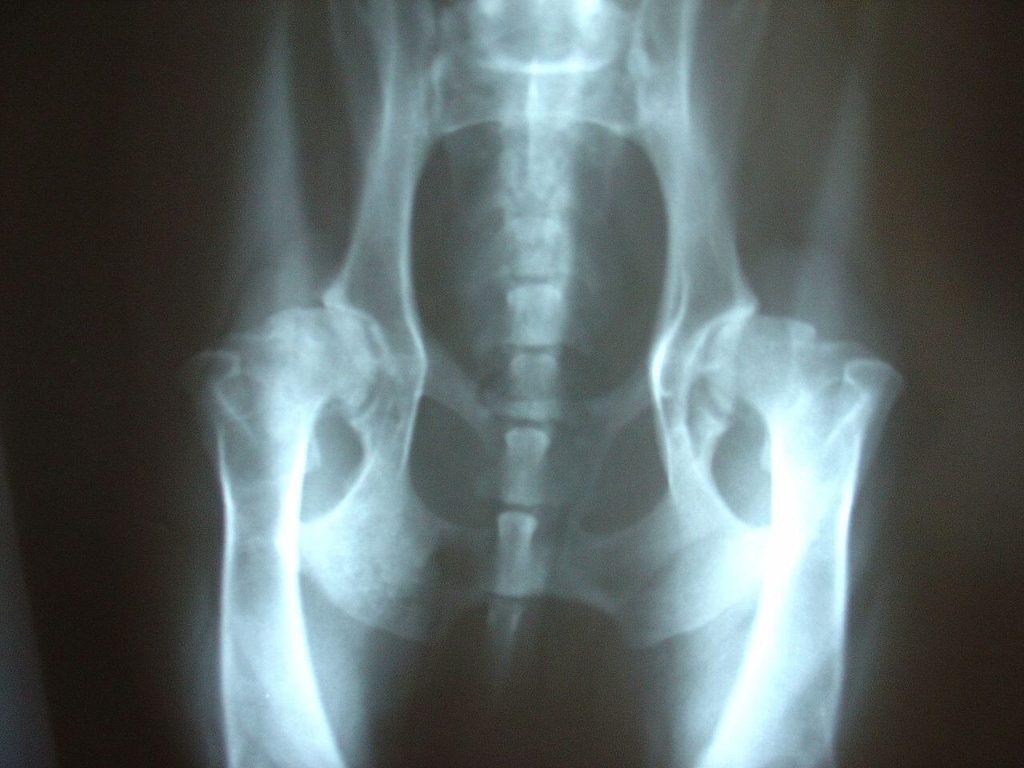

You have to realize that all of the activity we put our pups through stresses their joints. Every time they run, jump and use their joints they are prone to injury or tearing the ACL just like we are. But there can also be degenerative problems or developmental problems as well. If the dogs joint doesn’t develop properly then they may be prone to elbow or hip dysplasia. Some of the developmental problems that occur the most frequently in dogs are arthritis and secondary osteoarthritis that can be caused by cruciate ligament problems where the ligament causes instability due to its degeneration over time. Sadly, most dogs will unfortunately probably have some level of degeneration and arthritis as they age. The most common dogs to have these problems are the bigger dogs because they have more weight and size, which predisposes them to joint pain or other joint issues. Another factor is the breeding. Sometimes there are breeders out there who either don’t know that they are helping to breed dogs with higher predispositions for these problems, or they don’t care. Either way, if the breeding isn’t done correctly then there can be problems down the road. But the good news is, we have better options to treat these issues with than we used to and there is also improved diagnostics that can help diagnose the problem sooner and offer more treatment and support in the early stages.